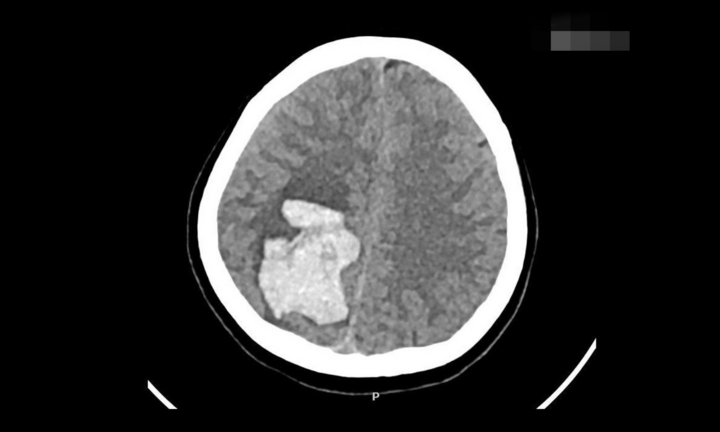

Đi chơi tàu lượn siêu tốc, người đàn ông 40 tuổi bị xuất huyết não

Sau chuyến du lịch, một người đàn ông 40 tuổi đã bị xuất huyết não và phải trải qua phẫu thuật để duy trì sự sống, nguyên nhân đến từ trò chơi tàu lượn siêu tốc.